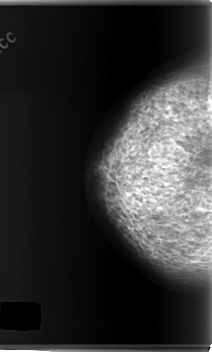

C_0148_1.RIGHT_MLO

RIGHT_CC LINES 5968 PIXELS_PER_LINE 3592 BITS_PER_PIXEL 12 RESOLUTION 50 NON_OVERLAY

RIGHT_MLO LINES 5920 PIXELS_PER_LINE 3544 BITS_PER_PIXEL 12 RESOLUTION 50 NON_OVERLAY